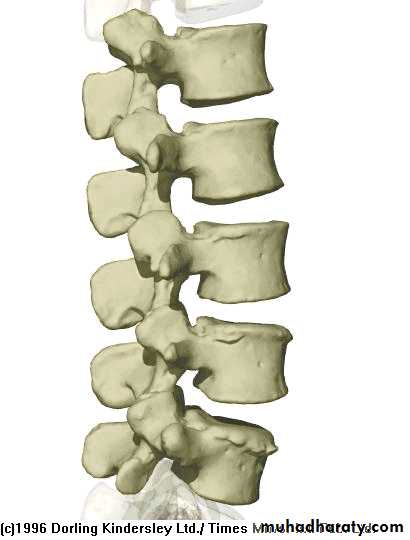

Lumbar Spine Anatomy

L1

L2

L5

L3

L4

Curvature is Lordotic

Facets are aligned vertically and allow bending

Vertebral body is kidney shaped in MRI